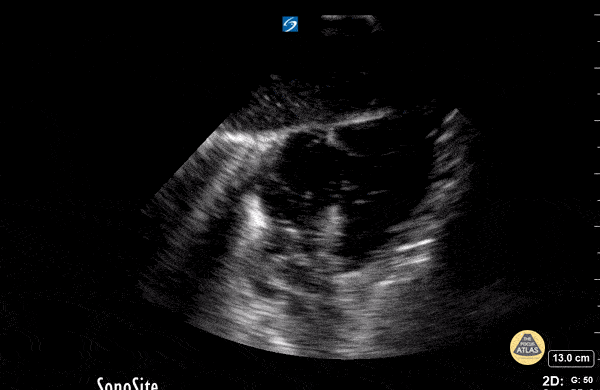

18 month old cardiac standstill

View: Unspecified Parasternal Long Axis Parasternal Short Axis Apical Four-Chamber Subcostal Four-Chamber Subcostal Inferior Vena Cava Right Upper Quadrant Left Upper Quadrant Suprapubic Longitudinal Suprapubic Transverse Subxiphoid Anterior Thoracic Phrenic